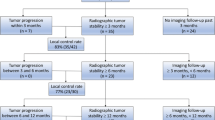

According to the Cardiovascular and Interventional Radiological Society of Europe (CIRSE) Quality Improvement guidelines for bone tumor management, the strategy of the interventional treatment can be curative or palliative (Fig. 5) [32].

(Adapted from reference [32])

Curative or palliative treatment for the management of BM.

Curative treatment can be proposed to selected oligometastatic patients presenting with limited bone disease (< 3 potentially treatable BM, each ≤ 3 cm in size). A series of prognostic factors favouring curative treatments have been identified: oligometastatic/metachronous status; the absence or limited cortical bone disruption; limited BM size (< 2 cm); long life expectancy; and good patient performance status [59]. Moreover, curative treatments may be indicated in patients with a slow-evolving disease [60], or in those presenting with a long-lasting stability of the systemic metastatic burden with one or few BM not responding to conventional systemic therapies (i.e., oligoprogression). Nevertheless, all the aforementioned conditions are generally uncommon and for this reason, only a few patients may benefit from curative treatments.

Only ablative techniques allowing tumor destruction may be used for curative treatment, which requires at least 5–10 mm safety margins to achieve effective local tumor control.

Palliative treatments may be proposed to the vast majority of patients with BM and are intended to manage one or more SREs:

-

If fractures should be prevented or treated, percutaneous osteoplasty or osteosynthesis is applied based on the predominant biomechanics of the affected bone and the features of the target BM (Fig. 6).

-

If pain management is needed and there is no risk of fracture, thermal ablation should be performed. Patients should be offered such treatment in case of focal pain (≥ 4/10 on a 0–10 visual analogic scale over the 24 h) corresponding to a focal BM on cross-sectional imaging. Ideally, ablation should target the interface between the normal bone and the BM; nevertheless, whenever possible, complete BM destruction should be achieved.

-

Tumor debulking can be achieved with ablation such as in the case of BM extending to surrounding soft tissues or spinal tumors growing quickly into the spinal canal. Nevertheless, it should be noted that local tumor control cannot be achieved if the BM has already invaded the anterior epidural space.

Despite the curative or palliative intent, when ablation and/or embolization are performed (or following RT), bone strength is impaired; and a substantial risk of secondary BiF exists. Accordingly, based on simple biomechanical consideration, interventional or surgical consolidation is mandatory to avoid a secondary BiF, which usually occurs within the first few weeks even though cases of delayed BiF have been reported [61]. Consolidation should ideally be performed during the same interventional session, or at the latest during the same hospital stay.